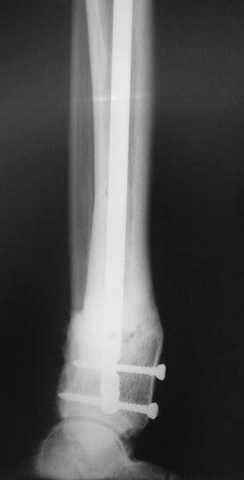

Реализовал описанную выше методику, и в итоге вот что получилось. Высылаю лишь прямые проекции,

в боковых тоже всё в тему.

внешний вид в аппарате - не завершающем этапе, сначала стопа тоже была фиксирована в аппарате.

Сейчас аппарат сняли, но случай ещё не завершенный.

Признаюсь честно, не совсем уверен в прочности консолидации на стыке косточек. Кроме того, укорочение в районе 6 см. Сейчас реабилитация - ходит опираясь на ногу с одним костылем.

Продолжение, видимо, будет... Возможно, будем удлинять.